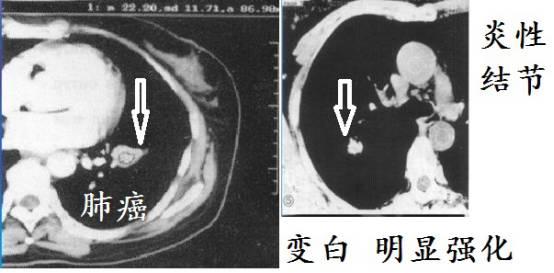

少增强

肺结核因为干酪性坏死,增强CT强化一般不明显!但是,有些肺结核在增殖阶段,生长活跃,没有形成明显坏死,有可能显著增强。这个要综合考虑。但是大多数肺结核增强一般不会显著强化。肺癌生长需要血供,常常显著强化。

简单的说,就是增强CT上,病灶越白,强化也明显,肿瘤、一般细菌感染引起炎性结节常常明显强化,肺结核强化不明显。

上图是肺结核增强CT,病灶几乎无强化,和下面差别很大。